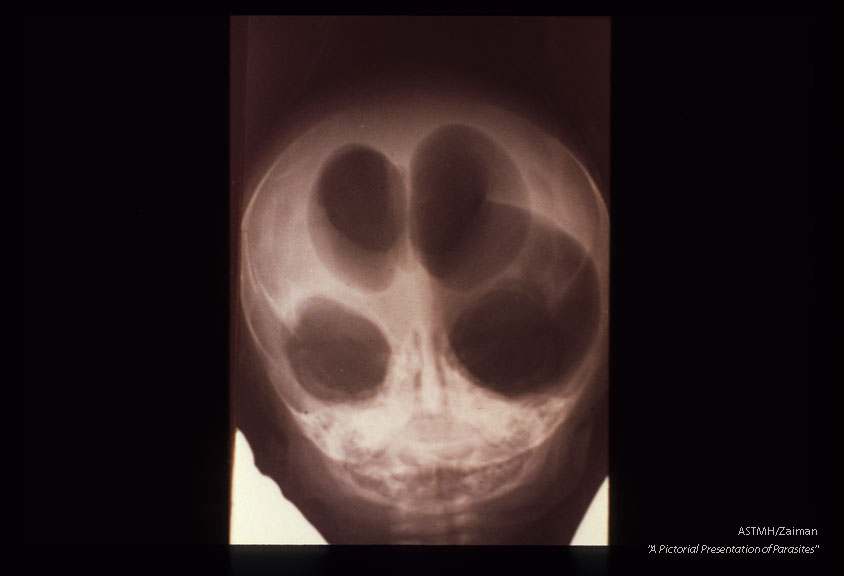

Encephalitis with hydrocephalus. Ventriculogram shows marked dilatation of ventricles.

Toxoplasma gondii

Description: Encephalitis with hydrocephalus. Ventriculogram shows marked dilatation of ventricles.